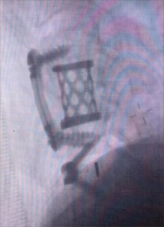

1.颈椎前路减压融合技术

颈椎前路减压融合术适用于①屈曲型颈椎骨折或骨折脱位所致的颈椎创伤性不稳定;②颈椎爆裂性骨折,椎体粉碎,压迫脊髓或脊髓前动脉,产生脊髓前综合征,需做前路减压,解除脊髓受压。③后路广泛性椎板切除,颈椎不稳,经后外侧融合仍不牢固。目前我科已成功开展前路ACDF技术、ACCF技术、ROI-C插片技术、Zero-P零切迹技术,具有创伤小、恢复快、疗效佳,早期下床活动的优点。